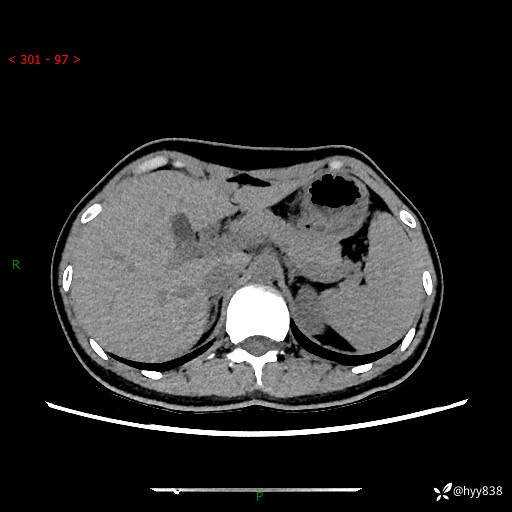

性别:女

年龄:23岁

简要病史:外院发现肝结节,来我院进一步增强确诊

上腹部CT平扫+增强

肝囊肿 (68)